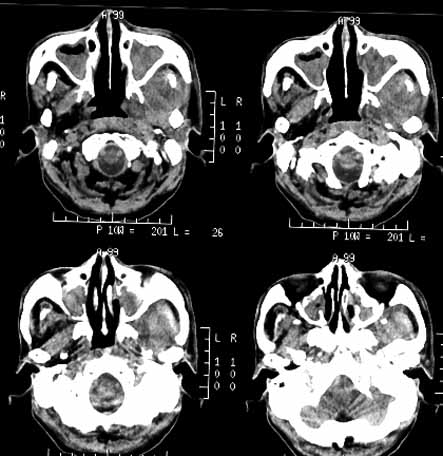

男性,60岁,鼻咽癌放疗后12年,5年前复发再行放疗后缓解。近期牙痛,牙龈活检见鳞癌细胞。

ct诊断:鼻咽癌复发,侵及左下颌骨、上颌骨及颞下窝。